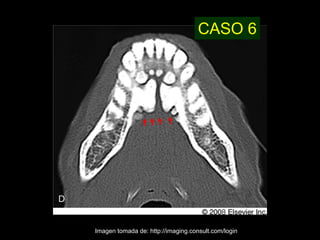

CASO 6

Imagen tomada de: http://imaging.consult.com/login

CASO 6 Imagen tomadade: http://imaging.consult.com/login